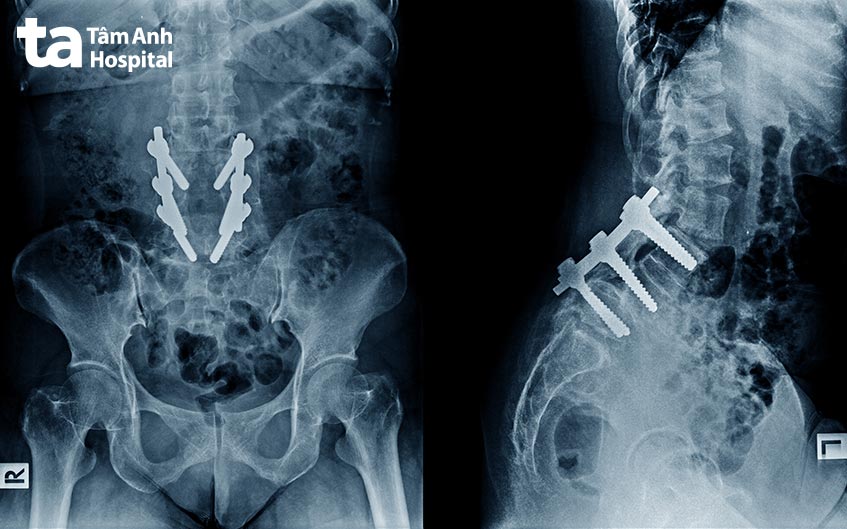

Người bệnh sẽ được gây mê để ngủ sâu và không cảm thấy đau đớn. Tiếp theo, bác sĩ tiến hành rạch một đường trên da tại vị trí cần ghép xương. Sau đó, phần xương thay thế sẽ được tạo hình vừa với vùng cần ghép, được cố định lại bằng những thiết bị như đinh ghim, đĩa, ốc vít, dây và cáp. Cuối cùng, bác sĩ sẽ tiến hành khâu vết mổ. Người bệnh cần phải sử dụng nẹp để hỗ trợ trong khi đợi xương lành hoàn toàn.